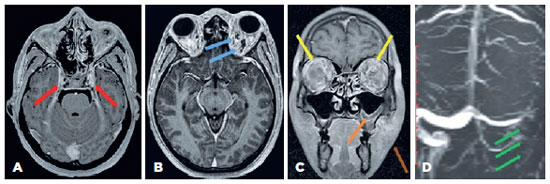

Magnetic resonance imaging (MRI) revealed proptosis of both eyes with diffuse, symmetrical soft tissue thickening and areas of enhancement with engorgement of orbital vessels and inflammatory fat stranding involving the preseptal, postseptal, intraconal, and extraconal spaces. Magnetic resonance venography (MRV) did not show flow-related enhancement at the left sigmoid sinus. T2-weighted MRI showed a persistent filling defect within the cavernous sinus on both sides and the left sigmoid sinus. The sphenoid, left maxillary, and left ethmoidal sinuses showed mucosal thickening with an air-fluid level (Figure 2).

12-fig02tb.jpg)

High-resolution CECT provides superb bone-air soft tissue details of the orbit and sinuses. CST may present as multiple irregular filling defects in the cavernous sinus on CECT. Our patient had normal CECT scan findings, similar to the report of Komatsu et al.(8). Thus, the managing clinician should have a high index of suspicion towards the diagnosis of CST based on clinical presentation, even if the CECT scan is normal.

High-resolution MRI visualizes the enlargement of the CST as filling defects over time. Thin-slice gradient recalled echo sequences with gadolinium contrast have been shown to be more sensitive than routine MRI pulse sequences for detection of filling defects in the cavernous sinus(9). MRV is helpful when the clinician suspects that dural sinuses are involved. In our case, MRI and MRV mapped out the complete extension of the CST in detail.